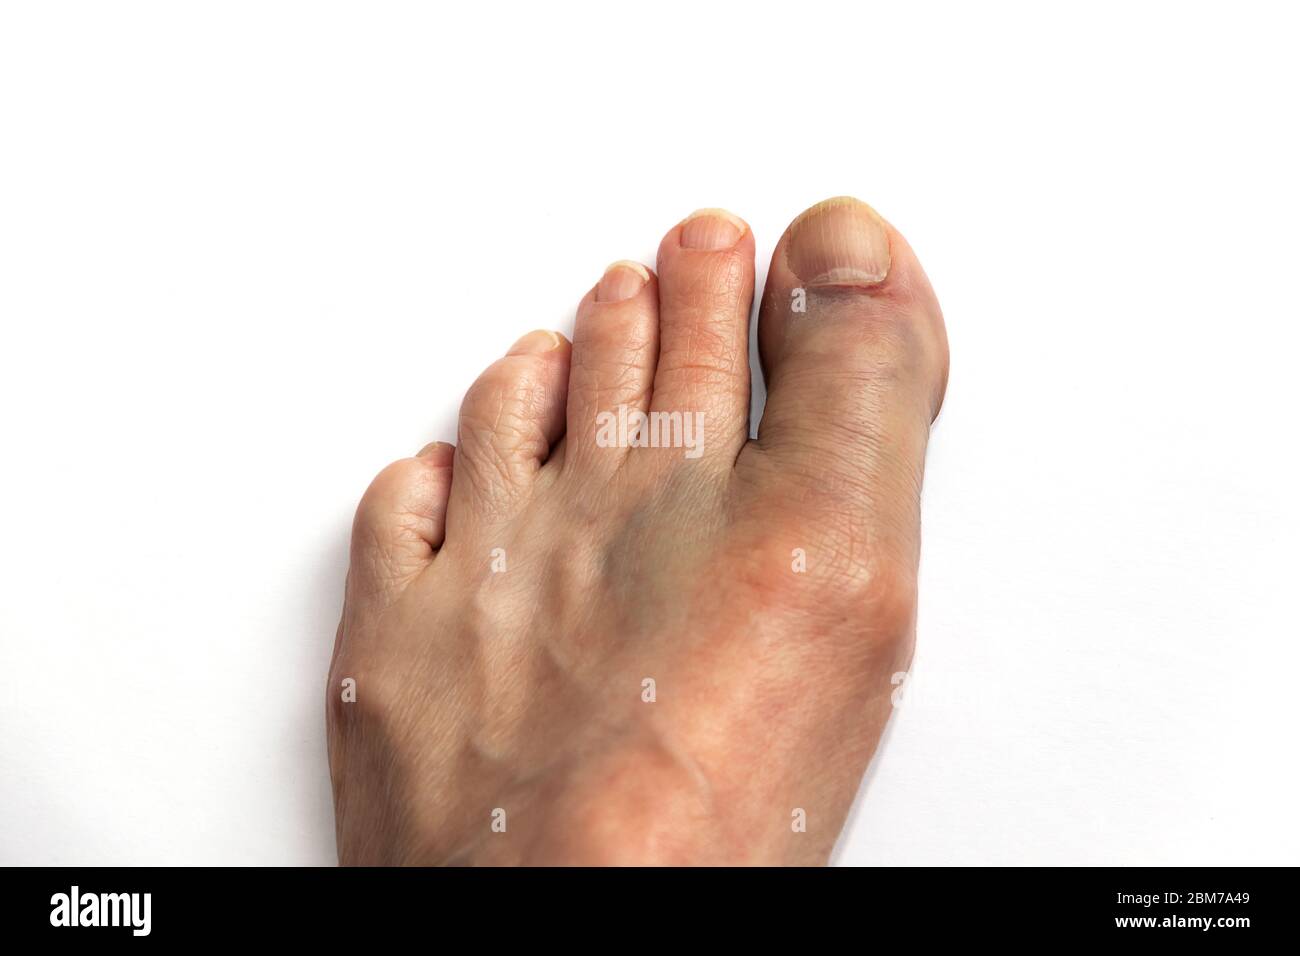

RF2HGHY1D–Schmerzhafter kleiner Zeh des asiatischen jungen Mannes. Verursacht durch gestrochene Zehen, gebrochene Zehen, eingewachsene Zehennagel, Bunions, Hühneraugen oder schlecht sitzende Schuhe.

RF3B12YK2–Eine Nahaufnahme der Füße zeigt signifikante Schwellungen und Blutergüsse am linken Fuß aufgrund einer Zehenfraktur, im Gegensatz zu einem gesunden rechten Fuß.